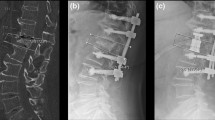

All procedures were performed under general anesthesia and according to the surgical guideline for vertebral body stenting by DePuy Synthes [24, 25]. Patients were placed in prone position on a radiolucent table. Access Kit 4.7 (DePuy Synthes Spine, Inc., Raynham, MA, USA) was utilized for transpedicular access. Under biplanar fluoroscopic-guidance, access instruments were advanced through two small skin incisions until they contacted the pedicle. After radiographic confirmation of the correct trajectory, instruments were advance through the pedicle and into the vertebral body, using a bilateral transpedicular approach. An access channel was created through trocars guided through the access instruments. The afterward inserted plunger was used to decide on the correct vertebral body balloon size. After advancement of two VBS systems through the corresponding channel into the vertebra, the VBS balloons were simultaneously inflated with a contrast-saline solution up to a pressure of 30 atmospheres until full balloon expansion was achieved followed by deflation and removal of the balloons, leaving the former surrounding stents in the vertebra to support the restored vertebral height. Under fluoroscopic guidance, polymethylmethacrylate (PMMA) cement (Vertecem V + , DePuy Synthes, Raynham, MA, USA) was injected bilaterally into the stent cavities until the stents were completely filled with some cement outside the stent interdigitating with the surrounding bone (Fig. 2). Depending on the underlying fracture type, the described procedure was followed by open or percutaneous posterior instrumentation. Postoperative regimen included supine positioning, immediate mobilization, pain medication according to the guidelines provided by the WHO, physiotherapeutic interventions and standing radiographs prior to hospital dismissal, 6 weeks, 12 weeks, 6 months and 12 months postoperatively.

Radiographic outcome measurements in a lateral view and b anterior–posterior view on plain lumbar x-rays. PH = posterior vertebral body height. MH = middle vertebral body height. AH = anterior vertebral body height. FKA = fracture kyphosis angle. SKA = segmental kyphosis angle. FSA = fracture scoliosis angle